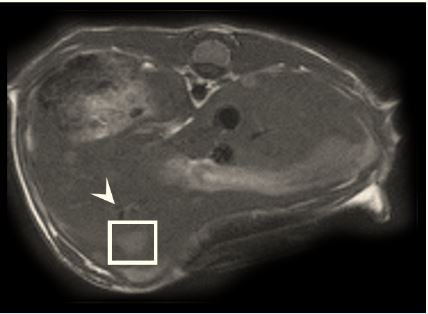

Fig2f Becker et al NovThe aim of this study was to investigate if there are any texture features that show a correlation with intrahepatic tumour growth before the metastasis is visible to the human eye. The experiments conducted on eight male mice showed that liver metastases may be detected by texture features before they become visually detectable by the radiologist.

Article: Radiomics of liver MRI predict metastases in mice

Authors: Anton S. Becker, Marcel A. Schneider, Moritz C. Wurnig, Matthias Wagner, Pierre A. Clavien and Andreas Boss